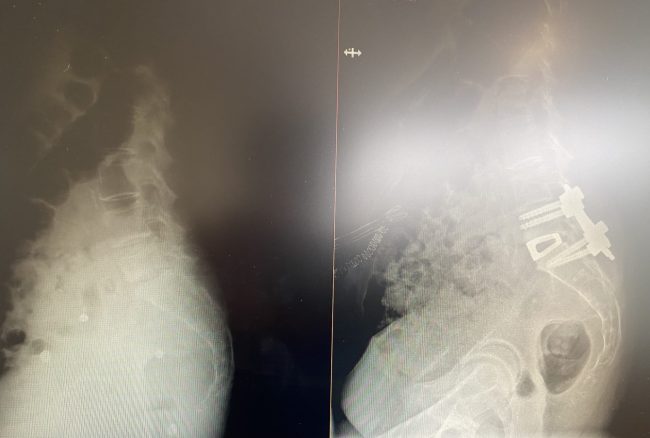

Fuente: Quirónsalud Huelva Es la primera intervención quirúrgica craneal realizada en el Hospital Quirónsalud Huelva Las cefaleas constantes, vértigos, dificultad en la marcha o entumecimiento de los brazos son algunos de los síntomas clásicos en un paciente que sufre la malformación de Arnold-Chiari. El doctor Miguel Ángel Roldán Serrano, neurocirujano del Hospital Quirónsalud Huelva…